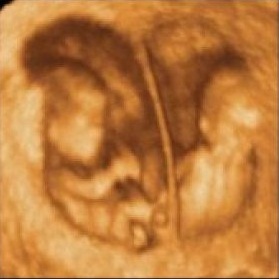

“Entonces el doctor me hizo allí mismo una ecografía, y tras la misma, me dijo que ahora todo lo veía muy claro y que ya sabía cuál era el mellizo que estaba enfermo. Mi marido y yo le preguntamos hasta en cinco ocasiones que si lo tenía claro y el nos dijo que sí”, ha rubrayado Gema.

Acto seguido, realizó una fetolisis selectiva -pinchar con una aguja fina, larga, hueca, a través de la barriga- al supuesto gemelo enfermo para paralizar su desarrollo e interrumpir el embarazo de dicho feto.

Pese a ello, a su vuelta al Hospital Puerta del Mar de Cádiz, y tras una ecografía, “se percataron que habían pinchado al feto sano y que el feto con el problema del corazón seguía vivo en el interior. No me lo creía”, recuerda. El feto tenía 20 semanas y un día de gestación en el momento de la intervención que ahora